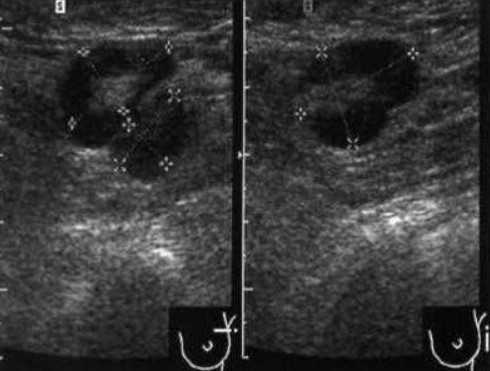

Практически во всех случаях дифференцировали лимфатический узел Кютнера (югулодигастральный), расположенный на границе средней и верхней трети шеи. Выявляемые лимфатические узлы имели размеры от 0,5 х 0,2 см до 2,3 х 0,8 см. УЗ-оценку производили после полипозиционного осмотра и нахождения самой длинной горизонтальной оси, что и принимали за максимальный поперечный диаметр. Большая часть лимфатических узлов (187) имели овальную форму с соотношением поперечного/переднезаднего более 1 (рис. 1 - 3). Тенденцию к округлению имели 30 лимфатических узлов, соотношение поперечного/переднезаднего приближалось к 1.

Рис. 1. УЗ-томограмма увеличенного реактивно измененного лимфатического узла: а - на фоне аденовирусной инфекции, б - после проведения противовоспалительного лечения

Мы установили, что, как правило, более округлая конфигурация лимфатического узла при его размерах, превышавших 10 мм, сопровождалась небольшими болевыми ощущениями, и более выраженной простудной (воспалительного характера) симптоматикой. Лимфатические узлы менее 10 мм чаще всего плохо пальпировались, либо вообще не выявлялись пальпаторно. Во всех случаях эхографически хорошо дифференцировался гипоэхогенный кортикальный слой и широкое, средней или чуть ниже средней эхогенности изображение области ворот лимфатических узлов. Четкость дифференциации составных частей лимфатического узла была снижена при размерах менее 5 мм. Мы отмечали различную толщину гипоэхогенного изображения области коры лимфатического узла: от очень широкой - при выраженности или прогрессировании воспалительного процесса, до узкой - на фоне положительной динамики.